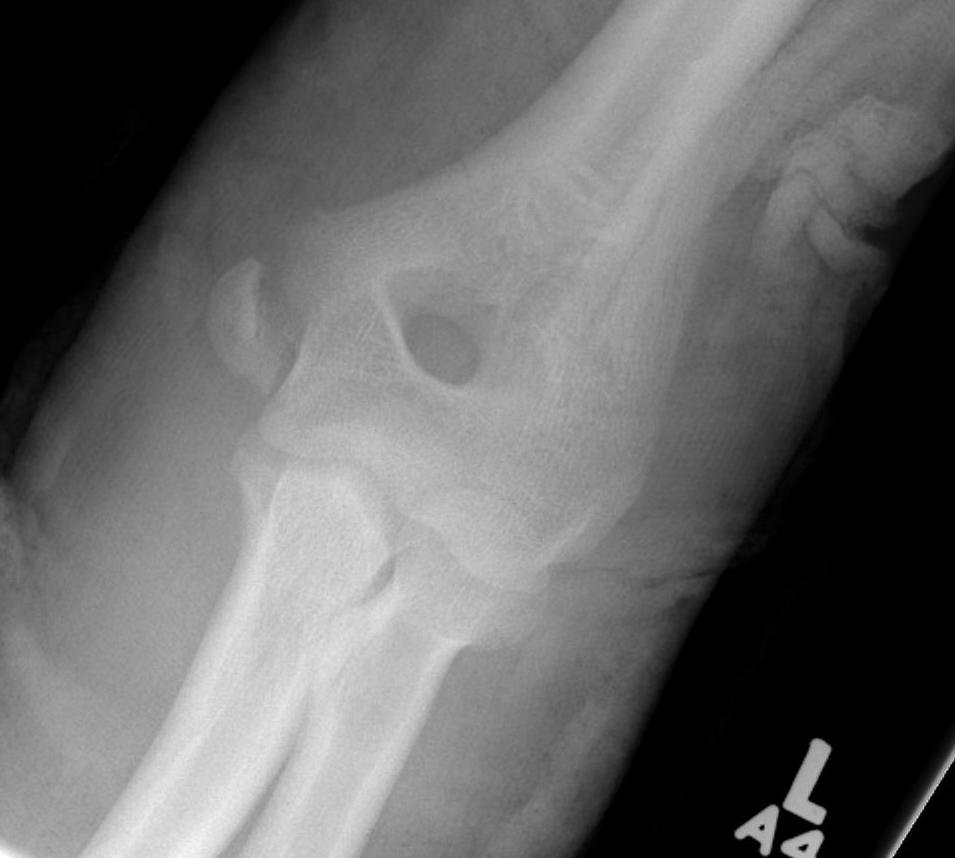

Medial Epicondyle / Condyle Fracture

Medial Epicondyle Fracture

Entrapped in joint

< 5 with dislocation

- medial epicondyle not visible

- may be entrapped in joint